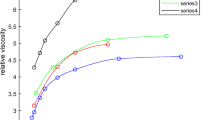

A mathematical model of aggregation and destruction of erythrocyte clots in the shear flow is constructed. Calculations show the influence of shear stresses in a blood flow on the mean dimension of clots. It is also shown that the sinuses of aneurysms create conditions for formation of large agglomerates, which can result in thrombosis of a blood vessel under consideration.